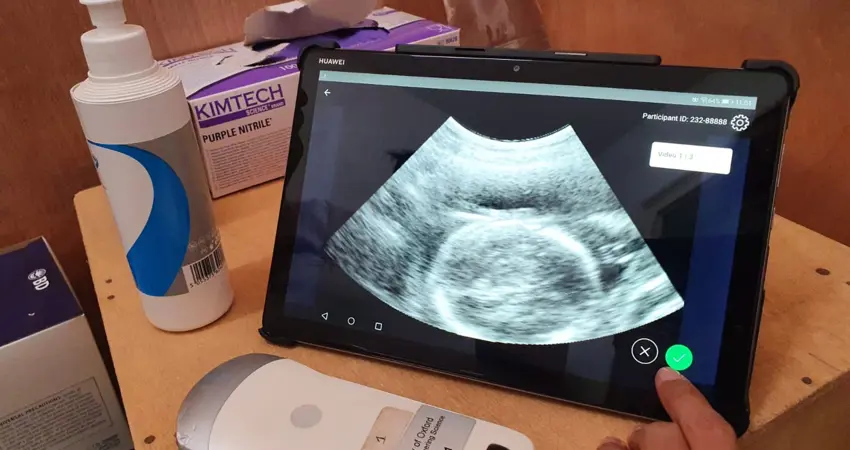

TraCer combines low-cost ultrasound equipment with artificial intelligence (deep learning) based image analysis algorithms

TraCer combines low-cost ultrasound equipment with artificial intelligence (deep learning) based image analysis algorithms to improve antenatal care and help improve pregnancy outcomes in low-and-middle-income countries (LMICs). Accurately estimating gestational age is a crucial tool in providing good pregnancy care, but the tools do so in LMICs are not always available. TraCer uses an Android tablet, low cost probe and bespoke software in a lightweight, portable system that runs on batteries. This means it can be used in areas where there is no reliable power supply.

Ultrasound video images are fed through automated algorithms which quality control the video and take measurements of the fetus to estimate gestational age. Unlike traditional sonography, it doesn’t require specific technical skills and can be used by health workers given minimal training.